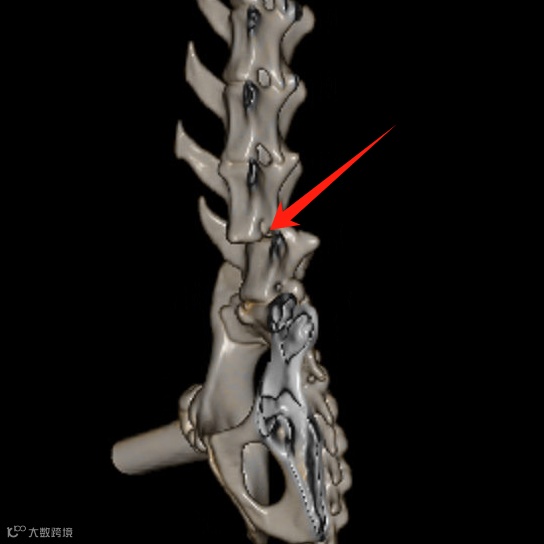

L6-7椎体错位,L7椎体相对于L6背移位,L6椎体连续性丧失,骨碎片掉入L6背侧椎管内,压迫马尾神经。